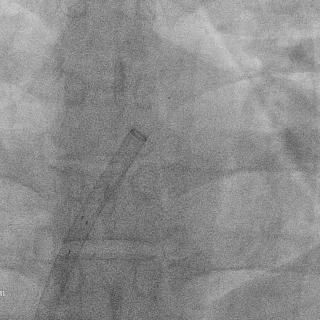

送入输送鞘

沿导丝送入输送鞘通过缺损,超声下可见鞘管呈“双轨征”

DSA下将前4个Mark点推出鞘管后,轻拉成型线使左盘面成型

再将输送系统整体后撤贴靠房间隔,超声下可见左盘贴合在房间隔上